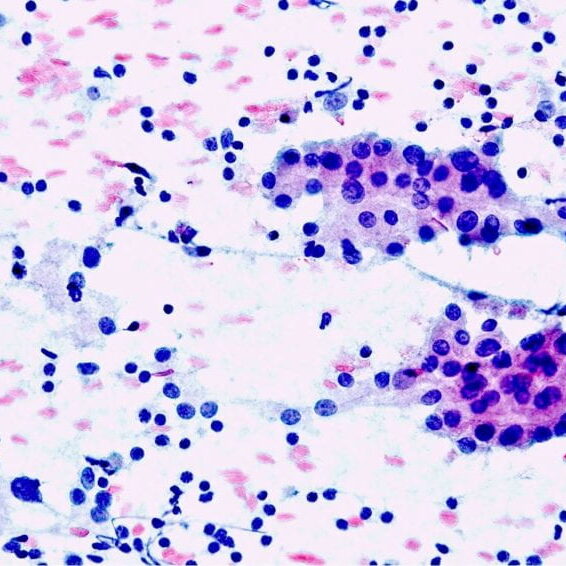

Welcome to the world of cytopathology!

for pathology residents and cytotechnologists, welcome to our cytopathology pages!

Cytopathology Team

National University Hospital, Singapore

National University of Singapore